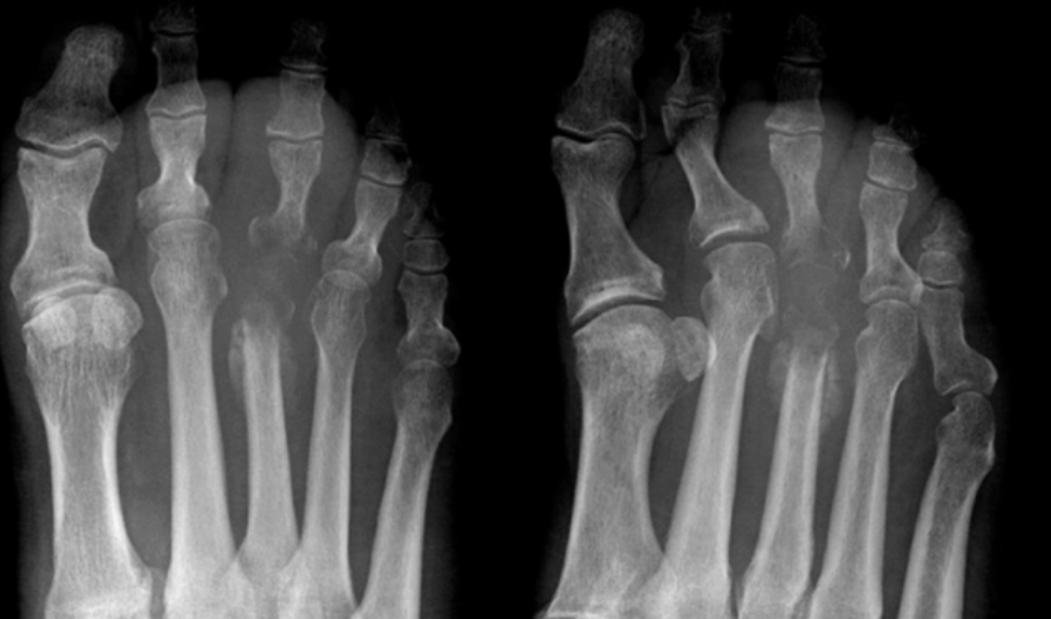

15

Q

Patient is radiographed 10 days after onset of forefoot pain.

Which structure is affected by avascular necrosis?

A

Third metatarsal head

Freiberg disease

16

Patient is radiographed 19 days after onset of forefoot pain.

What is the diagnosis?

What are two underlying conditions which may result in this specific diagnosis?

Diabetes, alcoholism

osteochondrosis (AVN) of metatarsal head (3rd)